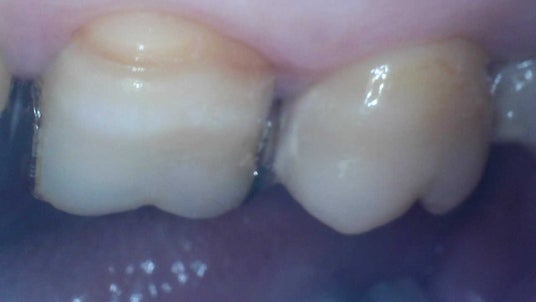

検査対象画像